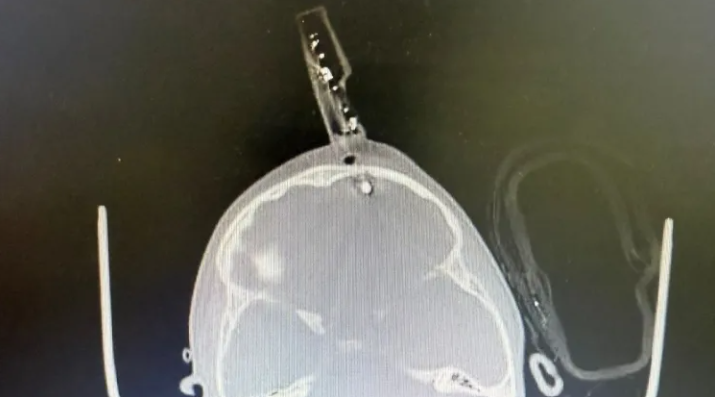

Uma tomografia computadorizada confirmou que o objeto havia atravessado o osso e atingido o tecido cerebral. O médico explicou que o crânio de crianças dessa idade possui apenas alguns milímetros de espessura, o que facilita fraturas e perfurações mesmo em quedas aparentemente simples.

Segundo o neurocirurgião Bruno Castro, responsável pelo atendimento, um dos pinos do carregador havia perfurado o crânio e estava fixado ao osso. Na avaliação inicial, a criança estava consciente, assustada e sem sangramento ativo.